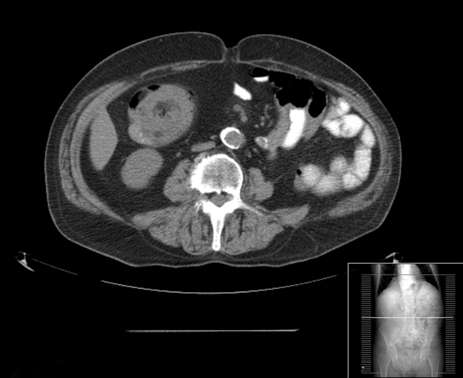

A 70-year-old male went to the emergency room with a 24-hour history of hematochezia preceded by pain in the right lower quadrant. The patient denied fever, weight loss, anorexia or vomiting. He was passing flatus and stools. His past medical history included ischemic heart disease, left renal neoplasia with nephrectomy two years previously and without evidence of recurrence, appendectomy in the childhood, right inguinal hernia repair, hyperuricemia, dyslipidemia, hypothyroidism treated with levothyroxine and colonic diverticula. On physical examination the patient was hemodynamically stable, afebrile and with pain on deep palpation of the right lower quadrant. Bright red blood was observed in the rectum. No other abnormal findings were noted. Blood tests demonstrated mild anemia (hemoglobin 11.2 g/dL) without leukocytosis or neutrophilia and elevation of C-reactive protein (88 mg/L). Renal and liver functions were normal. A colonoscopy was performed. Endoscopy revealed a violaceous mass with ulcerated/necrotic surface obstructing the lumen in the descending colon (Figure 1). After the colonoscopy the patient had an abdominal computed tomography scan that revealed a lipomatous ovoid tumor with 65 mm of major axis with origin in the ascending colon but with top ographic change, because of a complication: colic-colic intussusception with the typical donut sign (Figure 2). The patient underwent surgery that confirmed a lesion with 65 mm and origin in the colonic margin of the ileocecal valve that caused the intussusception. A right hemicolectomy was performed. The histopathology confirmed the diagnosis of giant lipoma with origin in the submucosa. | ||||||

Colonic lipomas are common findings during routine colonoscopy. They are benign lesions usually located in the right colon with decreasing incidence from the cecum to the sigmoid colon. They usually arise from the submucosal layer, but can extend into the muscularis propria, while up to 10% are subserosal. Classically, endoscopic findings described for lipoma are three: the mucosa being elevated over the lipoma with the biopsy forceps (tent sign), indentation of the lipoma with the biopsy forceps (cushion sign) or the "naked fat sign" where the fat can be extruded after biopsy. When typical endoscopic findings are present and they are asymptomatic lipomas do not need additional study or follow up. However, when the typical endoscopic findings are absent additional study with endoscopic ultrasound and/or surgical resection should be considered. Surgical resection should also be considered when they become symptomatic. Lipomas larger than 4 cm in size (giant lipomas) can become symptomatic in 75% of patients. They can manifest as abdominal pain, alteration in bowel habits, gastrointestinal bleeding, perforation, obstruction or intussusceptions. Intussusceptions are an uncommon complication of colonic lipomas and usually limited to one segment of the colon but can extend to more than one segment in some cases [1] [2]. Patients with this complication can present with abdominal pain and gastrointestinal bleeding. Abdominal computed tomography scan is the preferred diagnostic method, as the imaging characteristics of the tumors are typical for adipose tissue with the typical donut sign. Colonoscopy can show a mass with necrotic areas and ulcerated mucosa. Due to the nature of this lesion (subepithelial) biopsies are often inconclusive. The distinction between a colonic lipoma complicated with intussusception from other lesions (malignant epithelial or subepithelial) may be impossible based only on endoscopic aspects. Surgical resection is the treatment of choice when giant lipomas are complicated by intussusceptions. | ||||||